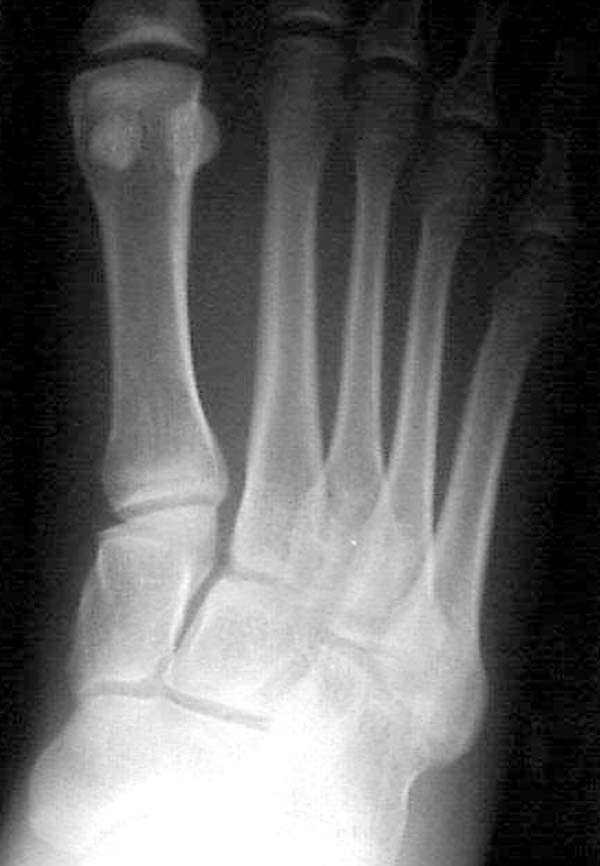

По снимкам нельзя исключить разрыв связки Лисфранка (связки между медиальной клиновидной костью и основанием второй плюсневой). Помогает в диагностике клиника (наличие изолированной гематомы на подошвенной поверхности стопы) и МРТ картина. Если связка повреждена - необходимо оперативное лечение.

По первому снимку, не видя больного, мог бы заподозрить перелом основания 3-й плюсневой кости. Поэтому избрал бы тактику консервативного лечения, как при переломе плюсневых костей без смещения!

Здесь КТ и сравнительные снимки стопы под нагрузкой.

Диагностировано повреждение медиальной и латеральной колонны.